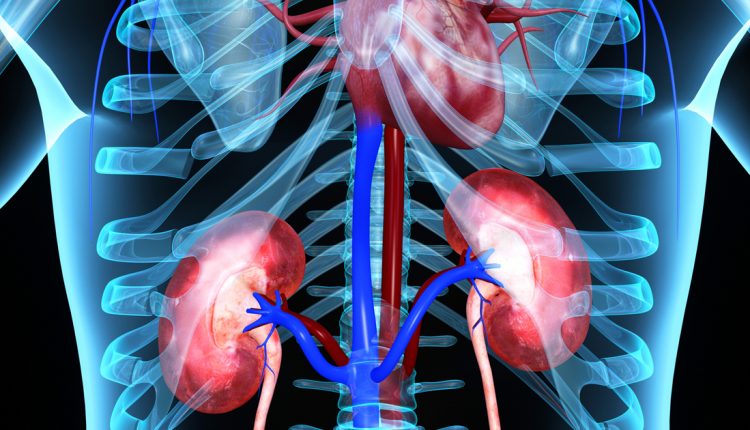

እቲ ኣገዳሲ ዝበሃል ኣገልግሎት እተን ክፋል ኣካላትና ዝኾና ኲላሊት፥ ኣብ መስርሕ ምፍራይ ቀያሕቲ ዋህዮታት ደም ዝገብራኦ ኣበርክቶ እዩ።

ስለዚ ኵሊት ሓንሳእ እንተተጐዲኣ ሳዕቤናቱ ብዙሕ ስለዝኾነ ኣብዚ እዋን ኣብ መላእ ዓለም ብዙሓት ሰባት ብሕማም ኲሊት ይሳቐዩ።